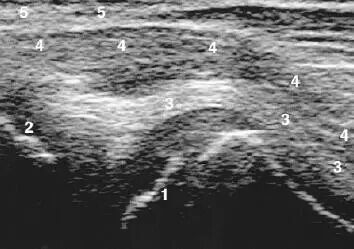

超声引导下包括两种进针方式:平面内注射(In-Plane Technique)( 即长轴入路,如图1) 和平面外注射( Off - Plane Technique ) ( 即短轴入路,如图2 )。超声成像下注射针呈高回声,平面外注射时有时不易辨认注射针的影像,可轻微移动注射针以便找到针尖。应根据临床实际选择进针入路,保证针在可视范围之内,采用各种针可视化增强技术来监测针的位置,在重要的结构周围,没有看到针尖不要贸然进针。BTX-A注射后,局部体积增加,呈低回声。

图1 平面内注射技术示例:探头、注射器位置及超声成像

图2 平面外注射技术示例:探头、注射器位置及超声成像(虚线表示进针入路)